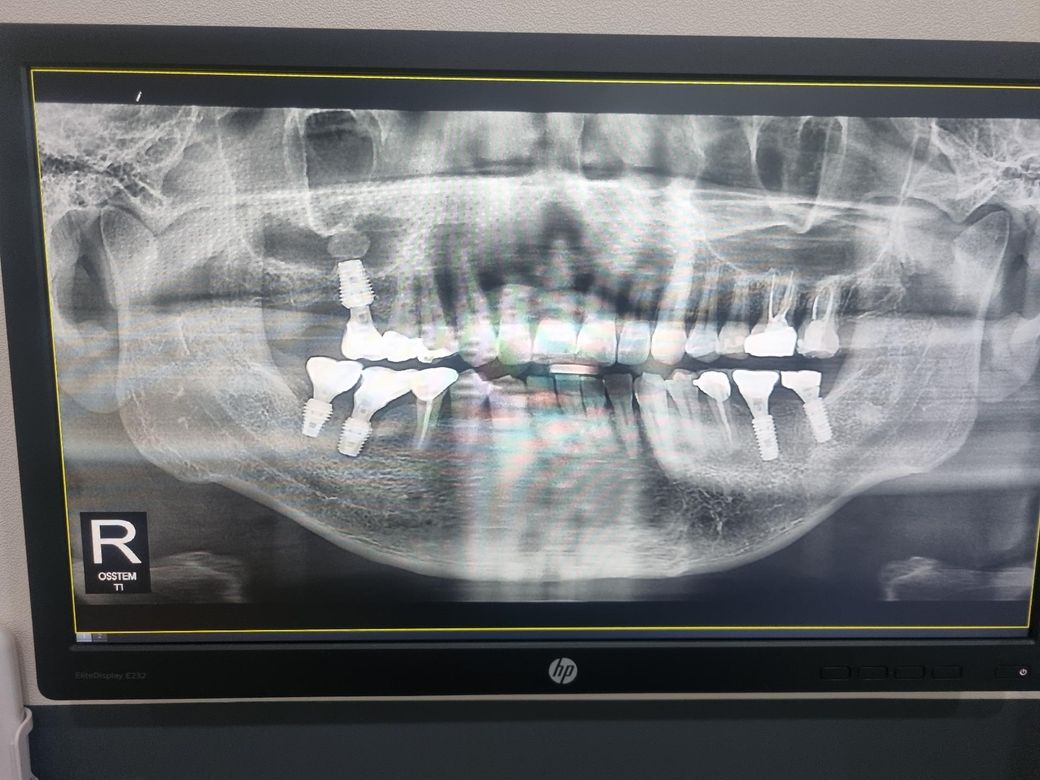

임플란트 통증 관련 문의 치과 엑스레이 첨부 합니다

오른쪽 상악 임플란트가 심은지 몇달이 지났는데도 통증이 안 사라지는데 이유가 뭘까요?

나사 위에 있는 동그라미는 염증일까요?

사진에 보이는 하얀색은 골이식제를 넣은것으로 보입니다.

뼈이식을 한 부분으로 보이며 사진만으로는 특별히 통증의 원인을 의심할 만한 것은 보이지 않습니다.

임플란트위에 잇는건 염증은 아니고 상악동 석처럼 보입니다. 상악동에 돌처럼 굳은 물질이 잇는걸로 계속 불편하시면 제거하는 수술을 하셔야될수도 있습니다.

엑스레이상 나타나는 흔적은 상악동 거상 및 뼈 이식의 흔적입니다. 엑스레이상에서는 특별히 임플란트나 임플란트 주위가 이상이 있어보이진 않습니다.

씹을때 불편하다면 교합조정을 받아보시고, 그 외 불편함이라면 임플란트 크라운을 잠시 제거해보고 증상 지켜보는 것도 좋습니다.